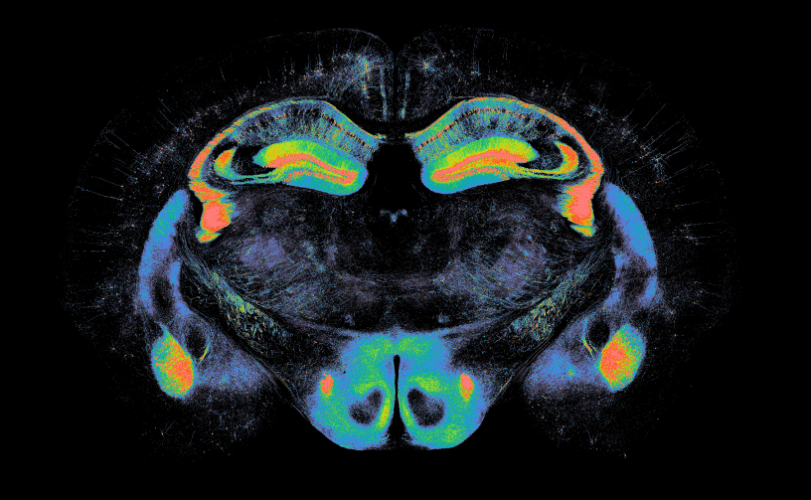

Quantitative analysis of lesions of renal foot processes and mitochondria by Structured Illumination Super-Resolution Microscope

In this study, Dr. Matsumoto et al. established a method for quantifying observed microstructural changes using the Fourier transform. When human renal biopsy samples were evaluated using this method, the degree of disruption of glomerular epithelial cell foot processes was correlated with the amount of urinary protein

Visualization and quantification of human glomerular epithelial cell structure disruption in EMT-stained sections

In patients with lgA nephropathy, it was observed that the higher the amount of urinary protein, the higher the degree of structural disruption of the foot process.

Visualization of glomerular epithelial cell structure disruption and mitochondrial damage in animal models

In a mouse model of tubular stromal disorders due to LPS administration or ischemia-reperfusion injury, mitochondrial fragmentation and swelling in tubular epithelial cells werw observed.